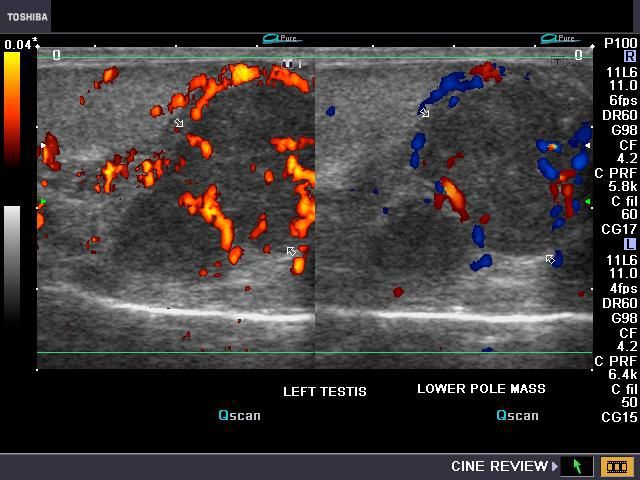

This adult, 48 yr. old male patient had a mildly painful mass in the left scrotum. Ultrasound image shows a hypoechoic, nodular mass of 3 x 2 cms. (appx.) below the left testis, involving the left epididymis (globus minor or tail) and the adjacent part of the left testis. The color and Power Doppler images (right) show considerable vascularity around and within the mass.Transverse sections (grey scale and color Doppler) images show a small hydrocele around the left testis.The scrotal skin also appears thickened.The right testis appears normal. Spectral Doppler imaging of the mass shows a low resistance flow within the vessels in this lesion. These color Doppler and ultrasound images show an inflammatory pathology of the left epididymis- typically these findings are those of left tuberculous epididymo-orchitis.